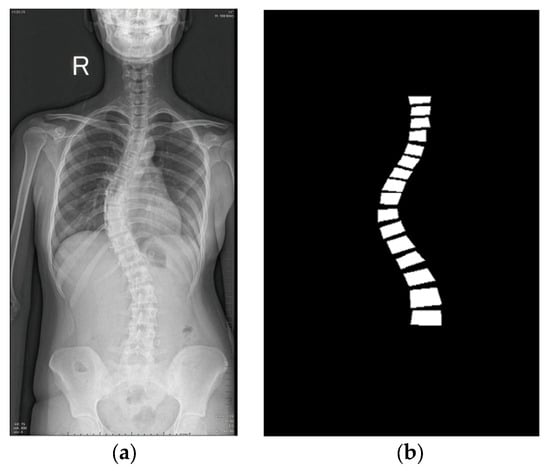

For learning-ready supervision, polygon vertices were denormalized to pixel coordinates and rasterized to produce a single-channel binary mask per image. An example radiograph and its derived mask are shown in Figure 4. Prior to dataset splitting, we conducted a manual quality-control review to remove corrupted/defective files (e.g., unreadable or truncated images) and clearly mislabeled annotations (e.g., polygons not enclosing the intended vertebra). The source contained 1018 radiographs; after this screening, 281 were excluded, yielding a final dataset of 737 radiographs with valid polygon annotations and corresponding masks.

Figure 4.

An example from the dataset [20]: (a) A raw X-ray image showing the patient’s right (R) side; (b) its masked image.

Both the radiographs and masks were resampled to 512 × 512 pixels. To minimize intensity loss, images were resized with area-based interpolation, whereas masks were resized with nearest-neighbor interpolation to preserve class boundaries. In the preprocessing pipeline, each image was read from the file system, converted to RGB, and paired with its single-channel (grayscale) mask, rescaled to 512 × 512 without exception. This standardization keeps all samples at a fixed spatial size so models can be trained directly without layers specific to dynamic resolutions. The filtered dataset was then partitioned at the image level into training/validation/test subsets of 82/10/8% (604/74/59 images). This pipeline—polygon-to-mask conversion followed by standardized splits—ensures supervision is consistent across heterogeneous inputs while avoiding ambiguity between detection-style boxes and the polygonal labels actually provided by the Roboflow dataset.